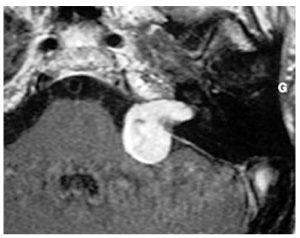

Quel est l’examen d’imagerie et sa séquence? Quel est le diagnostic? Quels signes cliniques ont pu conduire à la réalisation de cet examen?

IRM séquence T1 avec injection de gadolinium. Neurinome de l’acoustique de l’angle pontocérébelleux gauche.

surdité de perception avec atteinte rétro-cochléaire aux PEA

Sd vestibulaire harmonieux avec grand vertiges récidivants